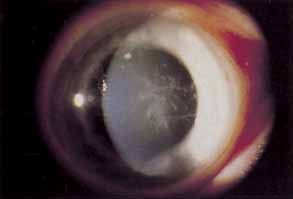

STERILE INFILTRATES

Sterile corneal infiltrates associated with contact lens wear are generally multiple, small, anterior stromal infiltrates found most often at the corneal limbus but also in clusters in the central cornea (Fig. 4).130–132 Rarely the epithelium alone may be involved and is commonly intact over stromal infiltrates. The anterior chamber may show mild to severe cellular reaction.130 Corneal infiltrates related to extended soft lens wear tend to form near the superior limbus.133 These infiltrates must be distinguished from their infectious counterparts, including chlamydia, by careful historical consideration and clinical examination.131 If there is any doubt regarding the etiology of the infiltrates, scrapings for stain and culture should be taken, followed by appropriate broad-spectrum topical antibiotic therapy.

Fig. 4 Twelve o'clock sterile marginal corneal infiltrate.

Using rigid gas permeable lens wear as the referent, soft lens wearers and particularly extended soft lens wearers carry a significantly higher risk of developing sterile infiltrates.6,9,130,134 PMMA lens wearers are the least likely to suffer this complication.134 A longer duration of soft lens wear provides a proportionately increased risk of developing these infiltrates.132,135 The rate of sterile infiltrates per year for disposable extended soft lens wear in a prospective study was as high as 7%, suggesting that disposable lenses are not the solution to this problem.136 Daily disposable soft lenses or soft silicone hydrogel lenses afford the lowest rate of peripheral infiltrates for soft lens wear.22,132